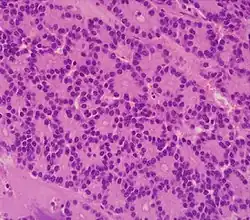

| Pancreatic neuroendocrine tumor | 5% | Multiple nests of tumor cells | ![]() |

|